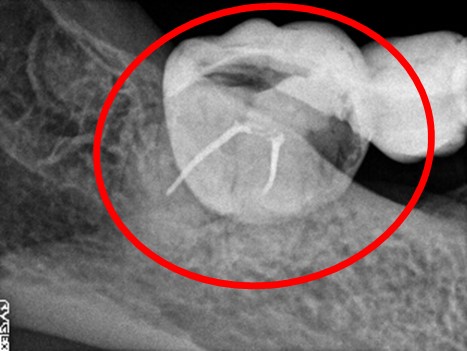

ブリッジの支台になっている奥の歯が、被せ物の中で虫歯になり、支台の役割を果たさず、前方の歯のみで支えられていました。前方の歯をそのままにして、後方の部分を切り離すと、そのまま取れてきました。中は、虫歯で歯根しか残っていない状況でした。この歯は、根管治療後、単独でオールセラミック冠を被せ、歯のないところにインプラントを埋入しました。

冠の中で大きな虫歯になり支台の役割を果たしていませんでした。

【インプラント埋入前】

冠はブリッジを切断しただけで取れてきました。軟化象牙質を取り除いたところ、歯根しか残っていない状況で保存できるかどうかのぎりぎりのところでした。